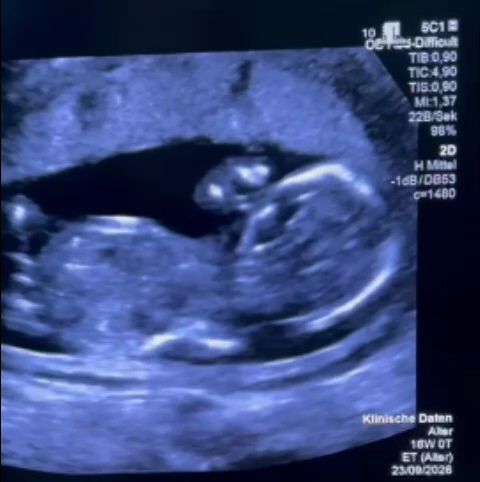

”Povestea Larisei începe la 12 săptămâni de sarcină, când medicul ginecolog observă o vezică urinară mărită şi recomandă un consult de medicină materno-fetală. Megavezica se tratează intrauterin prin montarea unui shunt vezico-amniotic de către un ginecolog supraspecializat. Fără intervenţie, presiunea din vezică distruge progresiv rinichii. În paralel, scade lichidul amniotic, esenţial pentru dezvoltarea plămânilor. Experţii europeni recomandă ca intervenţia să se facă între 11-16 săptămâni de sarcină”, explică Monica Althamer.

”Nu primeşte scrisoare medicală. Primeşte un raport de cinci rânduri referitor la ecografia efectuată. În ciuda discuţiilor halucinante, înspăimântătoare, raportul menţionează doar megavezica, fără alte anomalii. Este Joia Mare în Germania, ora 13. După o noapte nedormită, în maşină, mai sunt 8 ore de condus până acasă. Trebuie să confirme urgent internarea în Germania şi să plătească 13.000€. Ceva ce nu trebuia să plătească ei, pentru că au drepturi… Îşi iau cei doi copii şi pleacă spre Germania. Ajung în ziua de Paşte catolic. Se internează în regim de urgenţă. Profesorul Kohl o sună pentru a o încuraja. A doua zi shuntul este montat cu succes, în timp ce toată lumea aşteaptă, cu încordare. Trece cu bine prima şi cea mai grea noapte pentru bebeluş”, continuă relatarea.

Althamer distribuie, de asemenea, mesajul postat pe Instagram de către medicul german: ”Niciun drum nu e prea lung! În ultimul moment, o viitoare mamă din România a ajuns la noi (…) O consiliere extrem de slabă, mai ales că rezultatele tratamentelor noastre pentru această afecţiune sunt publice şi disponibile gratuit în PubMed, cea mai utilizată bază de date medicală din lume. Cu toate acestea, gravida a avut noroc în ghinionul ei: a întâlnit o doctoriţă care mă cunoştea încă de când era studentă. Am montat un mic stent în vezica fătului, care ajunsese deja cât capul lui. Dacă stentul rămâne bine poziţionat, vasele ombilicale sunt deschise şi există suficient lichid amniotic, evoluţia este favorabilă. Acum se întoarce acasă. Îi dorim drum bun şi tot ce e mai bine.”